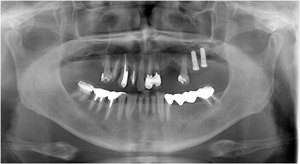

2﹒可快速將拍攝畫面導入影像軟體中,提供多項影像的操作功

......能例如:植牙、矯正.....等。

4﹒即時影像可跟病患即時溝通。

5﹒提升診療品質與看診效率。